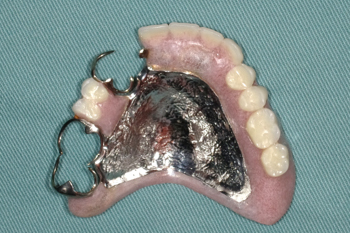

②金属床義歯

歯ぐきに触れる部分が金属で作られている入れ歯です。 金属にすることで入れ歯を薄くすることができるので、保険適用の入れ歯よりもしゃべりやすかったり、食べ物の温度も伝わりやすく、おいしく食事ができます。

金属なので耐久性に優れており、残っている歯への影響も少ないです。

自費診療(保険外診療)による入れ歯になります。

症例紹介

70代男性。修理を繰り返した義歯で噛みにくくなったために金属床義歯治療を行った症例。

治療内容:義歯の人工歯が摩耗していたうえに見た目にも支障があったため、噛み合わせの高さを挙上し、旧義歯に代わって、上下顎金属床義歯を製作しました。